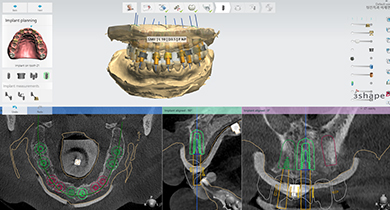

3D디지털 스캔을 통해 보다 안전하고 정확한 위치에 임플란트를 식립할 수 있고

출혈과 통증을 줄인 임플란트 수술방법 입니다.

첨단 진단장비를 이용하여 환자의 구강상태를 정확하게 분석합니다.

진단결과에 따라 환자에게 맞는 치료방법과 일정 등을 수립합니다.

3D디지털 스캔을 활용하여 가장 안전하게 임플란트를

식립할 수 있는 위치를 0.1mm 오차까지 정확하게 계산합니다.

제작된 보철물을 모의 수술을 통해 정해진 임플란트 식립 위치에 빠르고 정확하게 식립합니다.